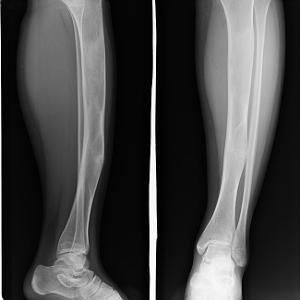

单发型病变部位在髓腔内,长管状骨的干骺端或骨干中心位或偏心位。骨皮质变薄形成缺损,呈模糊的髓腔内放射透明区,常形容为磨砂玻璃状。多发型纤维结构不良常累及数骨,同侧的髂骨、股骨、胫骨、腓骨常被累及。四肢长骨病变常累及骨的全部,髓腔宽窄不均,其增宽处骨皮质变薄并扩张。部分高度膨胀,其中有囊性改变,常表现为病理性骨折。X线表现为溶骨范围界限不清,骨皮质缺损和临近软组织肿块通常提示恶变。